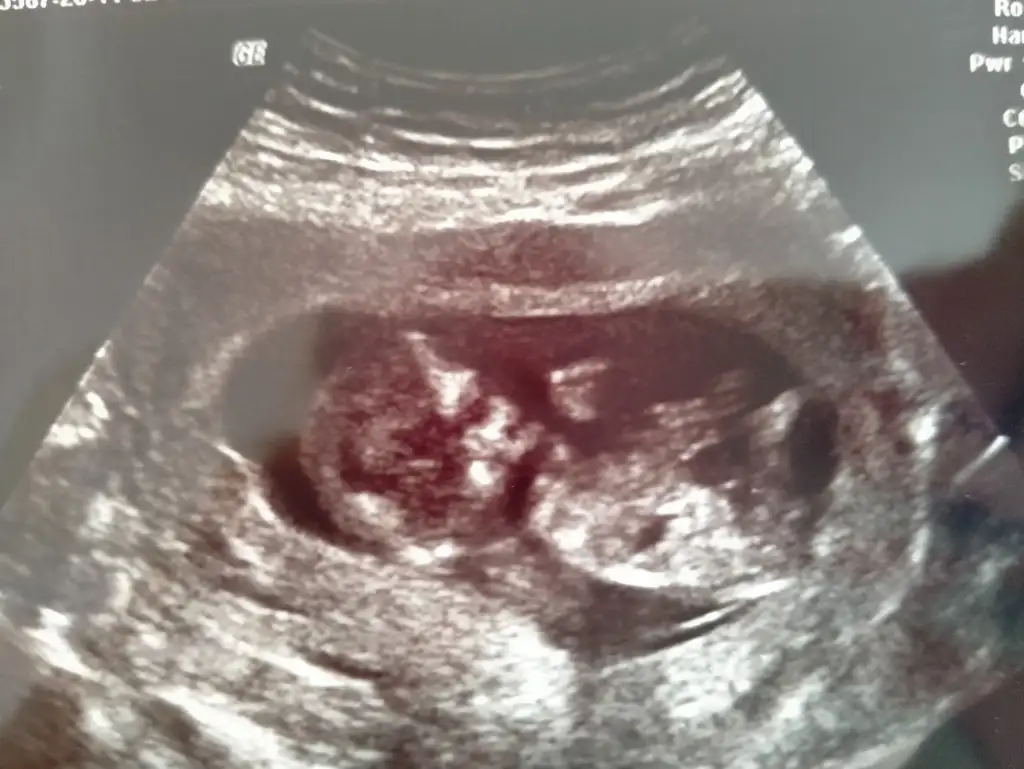

Nubu yüksek görünüyor sanki net değil karışık görünüyor emin olamadimBaşka usg yok doktor kıza benziyor demisti ama net değil demisti

Canım 11 de büyük olasılık kız 12 de nubu kalktı kız da olabilir erkek de dedi. 15 te %100 kız dedi 16 da hala kız dediSize 12.haftada doktor, erkek mi dedi?

Kız gibi sanki kaç haftalık usgler 11 12 13 haftalar olmalı

12 haftalıkKız gibi sanki kaç haftalık usgler 11 12 13 haftalar olmalı

Emin olamadım başka USG varsa paylaşın sanki erkek gibi gibi ama emin değilimMerhaba 11+0 tahminde bulunur musunuz?

Birde bu var :)Emin olamadım başka USG varsa paylaşın sanki erkek gibi gibi ama emin değilim

Net değil olursa 12 13 haftalar paylasirsinBirde bu var :)

Merhaba tahmininiz doğru çıktı doktorumuz %95 kız dediDr tam -----+ nubtan geçmiş ölçümü emin değilim sanki kız 11 12 13 haftalar olursa paylasin